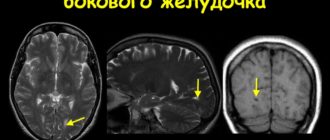

Дистанция затылочных рогов боковых желудочков

Последствия увеличения желудочков головного мозга у новорожденных Проводящая система головного и спинного мозга заполнена